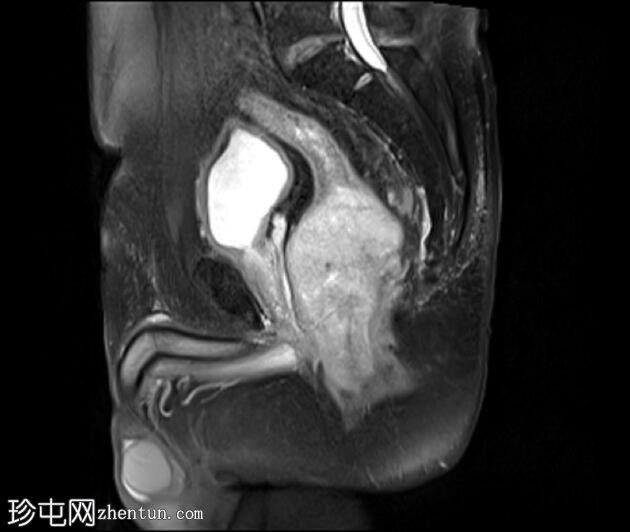

MRI

矢状位

PD加权像

可见一不规则分叶状肿块,累及直肠中段和远端,头尾方向长约7 cm,下缘距肛缘约2.5 cm。在T1加权像和T2加权像上,该病灶相对于骨骼肌均呈高信号。 PDFS(脂肪抑制)图像显示持续高信号强度,提示存在黑色素和/或出血成分。

增强扫描显示病灶内呈不均匀强化。直肠下段7点钟位置的系膜筋膜受累。后方系膜可见少量淋巴结。未见邻近器官侵犯。